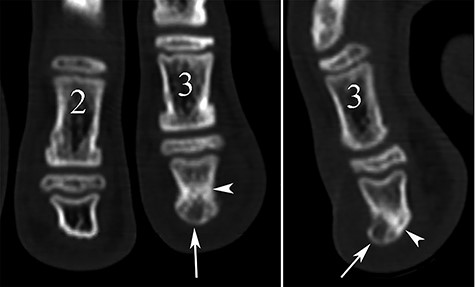

Conventional radiography showed a discrete deformation and irregular density of the phalangeal tuft (Fig. 2). The color Doppler ultrasound showed a hypervascularized pattern of swollen soft tissues on the dorsal aspect of the phalangeal tuft, suggesting a glomus tumor (Fig. 3). A CT scan showed a small lucent bone area within a focal hypertrophy of the phalangeal tuft with adjacent bone sclerosis (Fig. 4). Based on this latest examination, the diagnosis of OO of the distal phalanx was proposed as diagnosis.

CT reconstruction images showing a small central lucent bone area in the phalangeal tuft on the coronal plane (arrow in A) and a focal dorsal prominence of the tuft with lucent content (arrow) on the sagittal view (B). Note also the sclerosis of adjacent bone (arrowheads).

A diagnosis of glomus tumor was first considered in our case, because of the hypervascularized pattern in color Doppler ultrasound, and because of the pain that was caused only by compression or shocks against the lesion area. The glomus tumor is known to cause cortical erosion, but it is rare in children. In addition, the glomus tumor can be located against the bone but not within the bone, whereas in our case the radiolucent area was located inside a bony prominence of the phalangeal tuft, as shown in the Fig. 4. At the extremities (hand and foot), in a context of painless local digital swelling with inconclusive imaging, many other differential diagnoses are soft tissue tumors (malignant melanoma, mucoid cyst, epidermoid cyst, tenosynovial giant cell tumor, arteriovenous malformation …), other bone tumors (enchondroma, subungual Dupuytren’s exostosis …), and various other pathologies (inflammatory or microcrystalline diseases, infection, foreign body …).